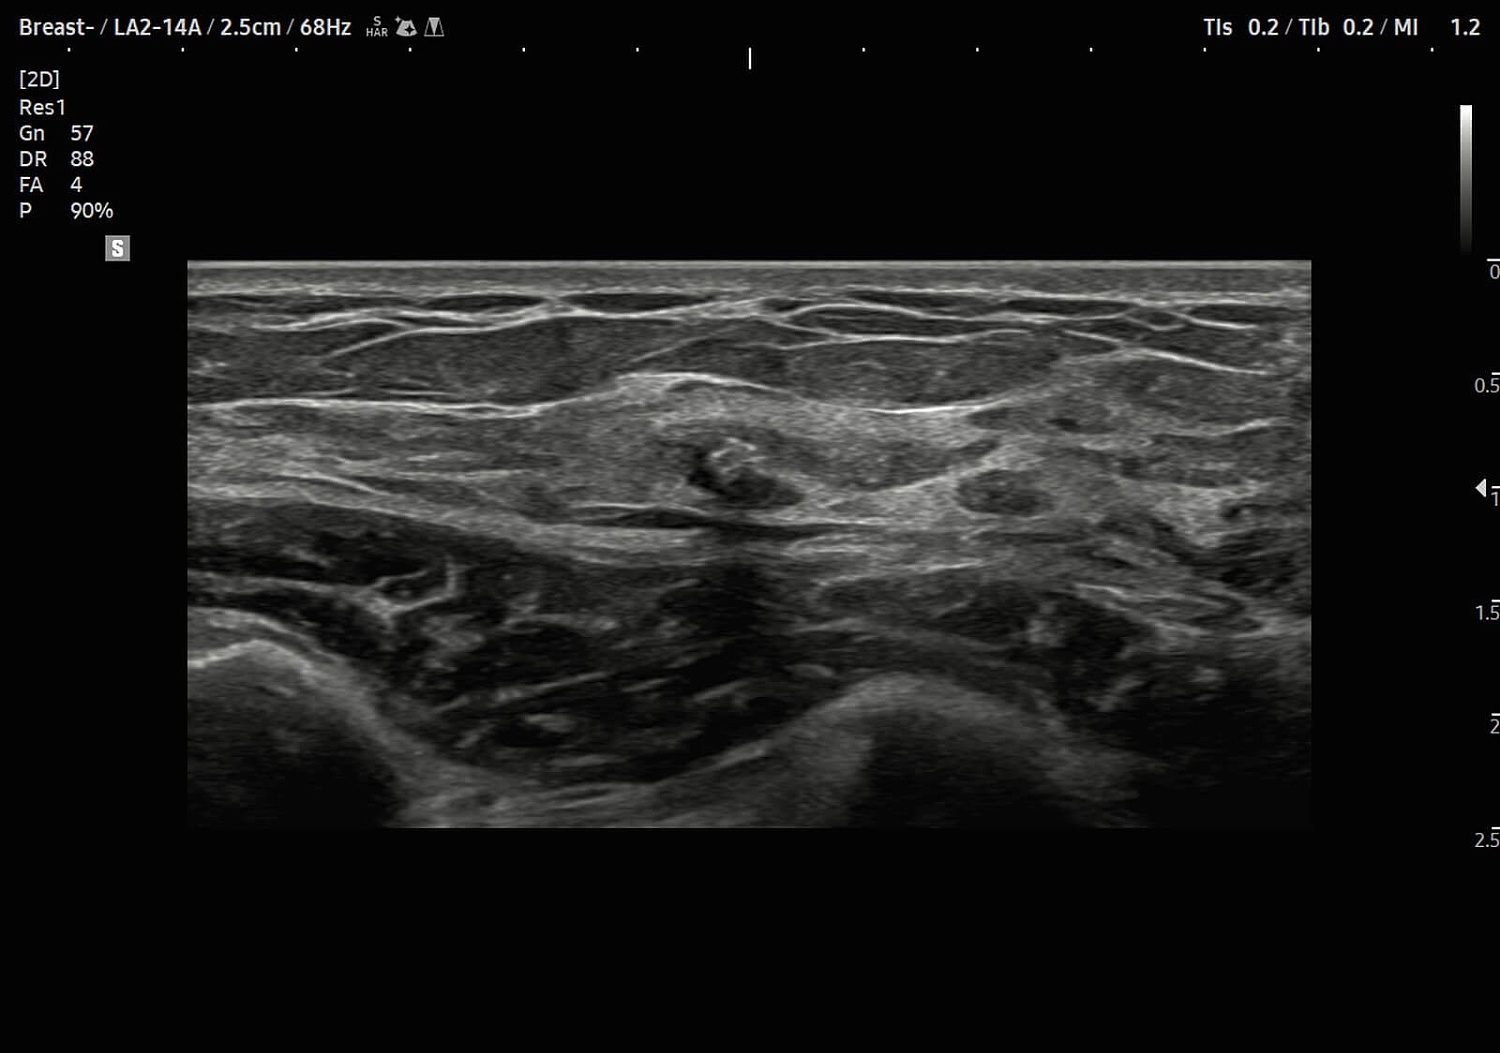

Рады сообщить, что в ассортименте нашей компании появился ультраинновационная УЗИ система экспертного (премиального) класса Samsung Medison V8. Этот ультразвуковой аппарат, функционирующий на базе искусственного интеллекта, предназначен для проведения исследований любого уровня сложности в области онкологии, пренатальной диагностики, неонатологии, гинекологии, урологии, а также общей радиологии, ортопедии, кардиологии и ангиологии.

УЗИ аппарат V8 отличается превосходным технологическим оснащением, высочайшим уровнем визуализации и удобством использования. Многочисленные решения позволяют оптимизировать рутинный диагностический процесс, автоматически осуществляя измерения, расчеты и классифицируя выявленные изменения. Это значительно сокращает время на исследование и в разы повышает диагностическую точность. Помимо уже знакомых функций Biometry Assist, AutoIMT, 2D Follicle, 2DNT и пр., в модели реализована опция автоматического сегментирования структур сердца, автоизмерения с технологией Heart Assist, определение положения срединного нерва в поперечном сечении Nerve Track.

- уникальную технологию изготовления датчиков — линейные монокристаллические датчики с ультраширокой полосой частот в пределах 1-14 МГц для максимальной визуализации поверхностных и глубоких структур, а также конвексные датчики с уменьшенной шириной сканирующей поверхности для повышения информативности при проведении исследований в области межреберья;